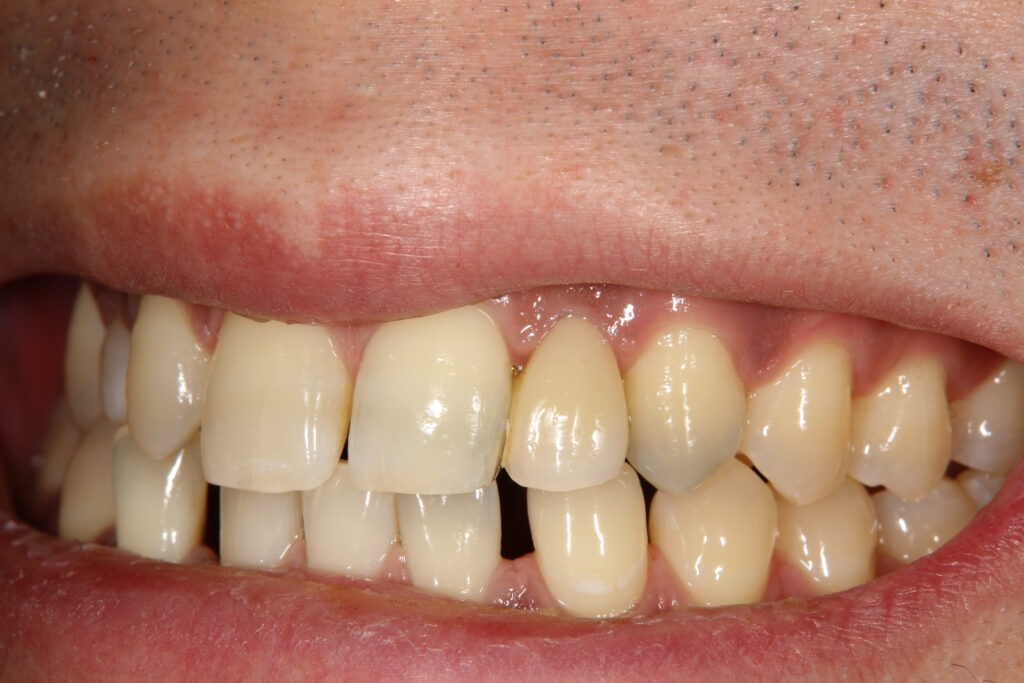

別の例として

同じ患者さんで保険診療の金属接着ブリッジと、自由診療のセラミック接着ブリッジをお口の中に入れて比較した写真ですが

比べてみると保険の金属接着ブリッジは金属が見えたり、透明感のない歯になっています。

セラミック接着ブリッジは金属が見えないのと透明感のある歯になります。